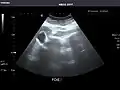

Aorta: Visualized portions normal in caliber, 16 x 15 mm.

Aorta -